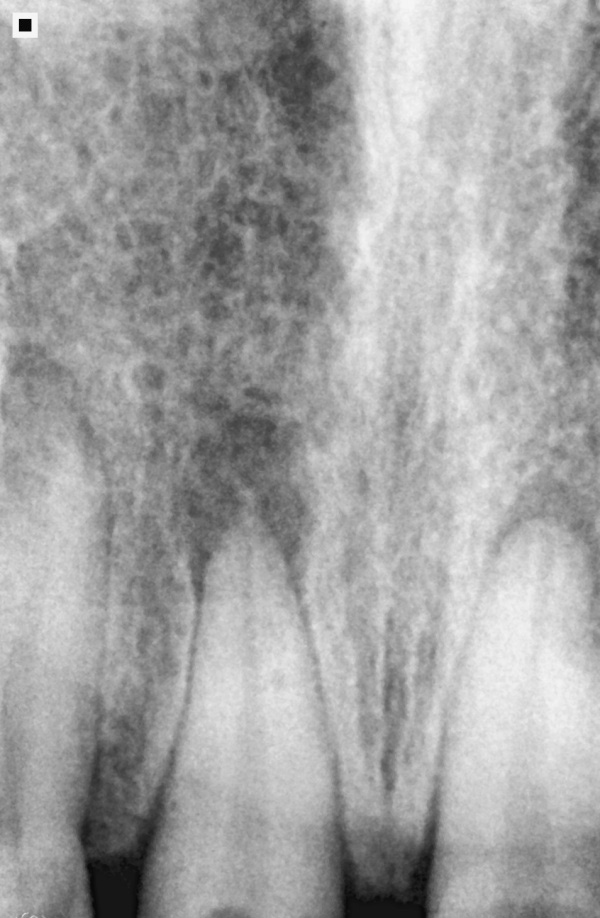

Initial radiography.